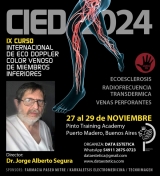

Temario del CIED 2024

La finalidad de este reconocido curso internacional Hands On es poner al día los conceptos básicos de la Ecografía Doppler aplicados al estudio de la enfermedad venosa crónica y su utilización en la realización de distintos tratamientos endovasculares venosos.